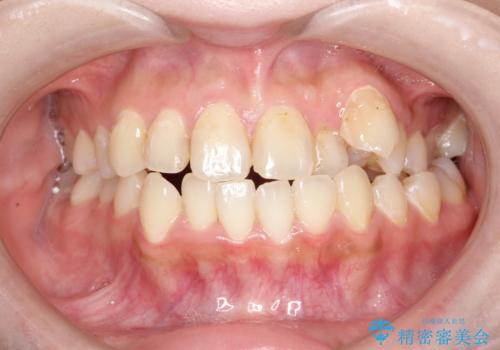

八重歯をインビザラインで非抜歯矯正

- 八重歯を主訴に来院されました。

インビザラインにて奥歯を後方に移動して八重歯が入るスペースを確保してく矯正する計画としました。

八重歯と前歯のガタガタがなくなり、歯並びがきれいになったのと、かみ合わせも改善することができました。